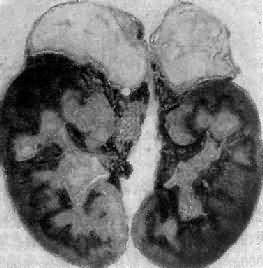

引起本病的病因主要有双侧肾上腺结核(图15-15)和特发性肾上腺萎缩,偶尔也可因转移癌引起。特发性肾上腺萎缩(idiopathic adrenal atrophy)是自家免疫性炎症,故又称自家免疫性肾上腺炎(autoimmue adrenalitis),多见于青年,女性显著多于男性。病人血中常有抗肾上腺皮质细胞线粒体或微粒体抗体,常与其他自家免疫性疾病合并。双侧肾上腺高度萎缩,共重2.5g以下;皮质菲薄,镜下除皮质萎缩外,有大量淋巴细胞和浆细胞浸润。

图15-15 双侧肾上腺结核